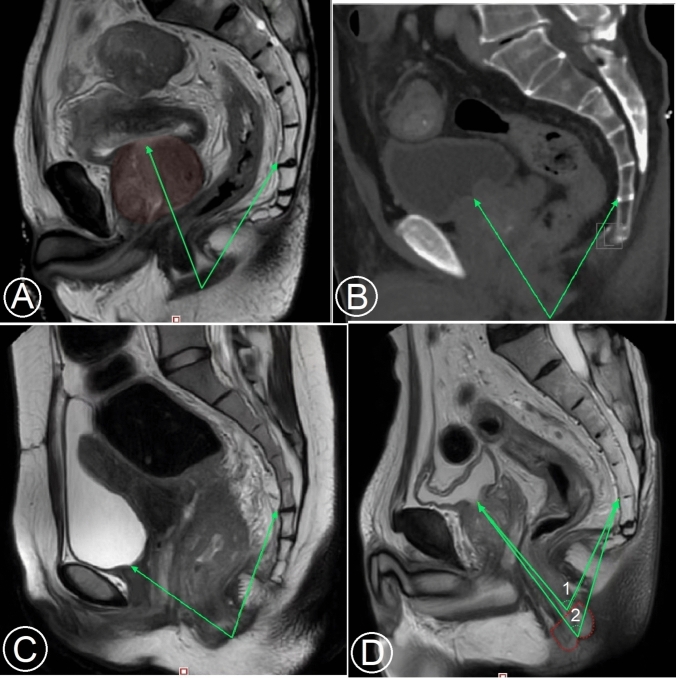

Methods: A total of 264 male patients who underwent total mesorectal excision (TME) due to primary rectal cancer located in the mid and low rectum (distal tumor margin distance from the anal verge ≤ 7 cm) were retrospectively included in the study. An angle SAU° [formed by two lines: line 1 (connecting the anteroinferior border of the fifth sacral vertebra and center point of anus) and line 2 (connecting internal urethral orifice and center point of anus)] was measured using the built-in software of MRI for every patient. The patients were categorized into four groups according to the angle SAU° and BMI. The operative time, estimated blood loss, TME quality, and anastomotic leakage (AL) were compared between group 1 and group 2 as well as between group 3 and group 4.